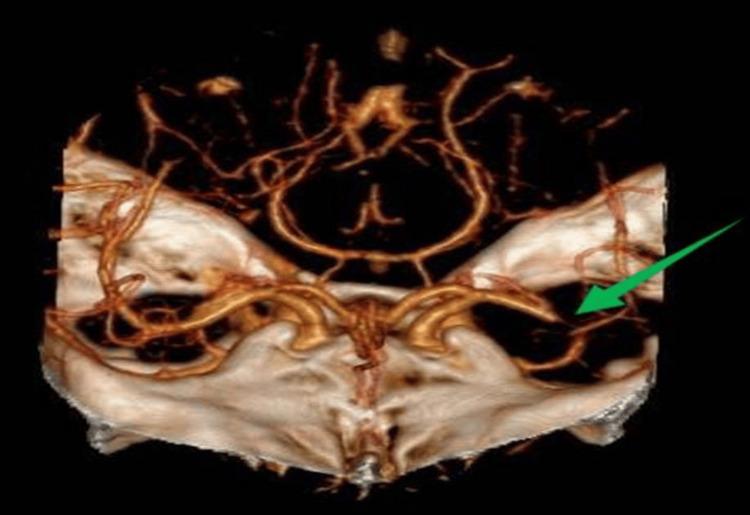

Infective endocarditis (IE) is a rare but serious life-threatening disease, often presenting with highly variable clinical symptoms. Risk factors for this condition include valvular heart disease, age, medical procedures, dental procedures, and intravenous drug use. Patients with IE may exhibit valve dysfunction, heart failure, or neurological complications such as stroke, the latter being caused by an embolus originating from valvular vegetations that occlude more distal vessels in the cerebral circulation. Diagnosis is based on the modified Duke criteria. We report a case of a 20-year-old male patient who presented to the emergency department with the acute onset of aphasia, right-sided hemiparesis, and fever. Neurological examination revealed a National Institute of Health Stroke Scale score of 10, and computed tomography (CT) angiography confirmed a left middle cerebral artery occlusion. Since endocarditis was not known at the time of stroke diagnosis, the patient underwent thrombolysis. He then underwent thrombectomy with successful recanalization, and the retrieved thrombus was sent for microbiological analysis. Laboratory findings showed leukocytosis, elevated erythrocyte sedimentation rate, and elevated C-reactive protein, and both blood and thrombus cultures were positive for . An echocardiogram revealed a vegetation in the mitral valve, confirming the diagnosis of IE. The patient was treated with ceftriaxone, rifampicin, and gentamicin according to antibiotic susceptibility results, and underwent mitral valve replacement surgery, demonstrating a good clinical outcome with recovery from the neurological deficits. This case highlights the importance of considering the diagnosis of IE in patients presenting with stroke and fever, as ischemic stroke can be an embolic complication of IE. It also emphasizes the potential role of microbiological analysis of clots retrieved through thrombectomy in identifying the infective agent, especially in patients where blood cultures are negative or inconclusive. Such identification might help select appropriate antibiotic therapy, although more studies are required to better define its role in patient care.

感染性心内膜炎(IE)是一种罕见但严重的危及生命的疾病,通常表现出高度可变的临床症状。该疾病的危险因素包括瓣膜性心脏病、年龄、医疗操作、牙科操作和静脉药物使用。IE患者可能出现瓣膜功能障碍、心力衰竭或神经系统并发症,如中风,后者是由源自瓣膜赘生物的栓子引起的,该栓子会阻塞脑循环中更远端的血管。诊断基于改良的杜克标准。我们报告一例20岁男性患者,他因急性失语、右侧偏瘫和发热就诊于急诊科。神经系统检查显示美国国立卫生研究院卒中量表评分为10分,计算机断层扫描(CT)血管造影证实左大脑中动脉闭塞。由于在中风诊断时未知患有心内膜炎,该患者接受了溶栓治疗。然后他接受了血栓切除术,血管成功再通,取出的血栓送去进行微生物分析。实验室检查结果显示白细胞增多、红细胞沉降率升高和C反应蛋白升高,血液和血栓培养均对 呈阳性。超声心动图显示二尖瓣有赘生物,证实了IE的诊断。根据抗生素敏感性结果,该患者接受了头孢曲松、利福平和庆大霉素治疗,并接受了二尖瓣置换手术,临床结果良好,神经功能缺损得以恢复。该病例强调了在出现中风和发热的患者中考虑IE诊断的重要性,因为缺血性中风可能是IE的栓塞并发症。它还强调了对通过血栓切除术取出的凝块进行微生物分析在识别感染病原体方面的潜在作用,特别是在血培养阴性或不确定的患者中。尽管需要更多研究来更好地确定其在患者护理中的作用,但这种识别可能有助于选择合适的抗生素治疗。